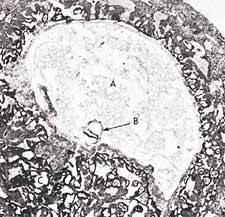

شکل 3: در این فتومیکروگراف، تعلیق یک جنین (با علامت B) را در مرحله علقه (حدود 15 روزه) در رحم مادر مشاهده میکنیم. اندازه واقعی جنین در این مرحله حدود 0.6 میلی متر است.